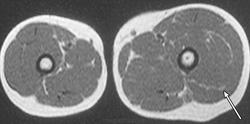

Клинические проявления заболевания характеризуются выраженным полиморфизмом. Наряду с типичной симптоматикой - парциальным гигантизмом рук и ног, гемигипертрофией, артериовенозными аномалиями, макроцефалией - наблюдаются разнообразные опухоли: бородавчатый эпидермальный невус, гемангиомы, лимфангиомы, липомы, гамартомы. Иногда отмечаются косоглазие, экзофтальм, миопия, прогения, варикозное расширение вен, разрастание кожи на подошвах. Примерно в 55% случаев выявляется умственная отсталость, в 13% - судорожный синдром. Наблюдались также больные с изолированной макродактилией, спленомегалией, избирательной патологией глаз и черепа в виде множественных менингиом, полимикрогирии, ретинальной пигментной дегенерации и атрофии зрительного нерва. Продолжительность жизни пробандов, как правило, невелика и колеблется от 3 до 40 лет. Смерть наступает чаще от злокачественных новообразований. Описаны такие опасные для жизни осложнения, как венозные тромбозы и эмболия легочной артерии. Так, A. Stavotinek и соавт. в 2000 г. сообщили о 3 больных, умерших в возрасте 12, 17 и 25 лет от эмболии легочной артерии [9].